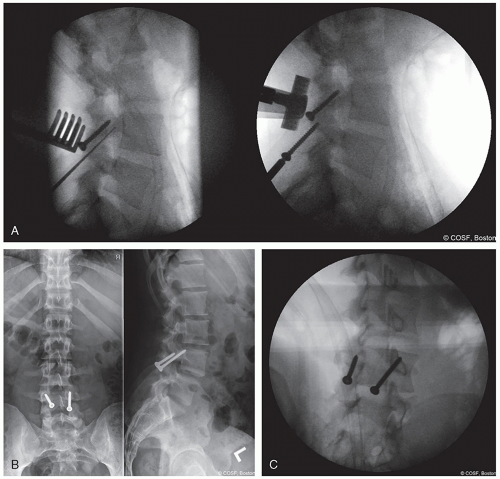

Buck screw technique (Figure 7.2A-C)

Preoperative CT to confirm lamina intact—absence of bifid lamina

Use fluoroscopy and K-wire to plan path for cannulated drill AP and lateral fluoroscopy

Burr starting point at inferior aspect of ipsilateral lamina

Percutaneous insertion of threaded guide pin for cannulated drill inserted midline and distal to incision, angled lateral and ventral under fluoroscopy

Advance guide pin to pars defect

Place bone graft

Advance guide pin to anterior superior cortex

Drill over wire and far cortex

Remove wire and place solid 4.5 mm screw—bicortical

Repeat on contralateral side

Decorticate base of TP and lamina

Place additional bone graft on lamina

Close wound